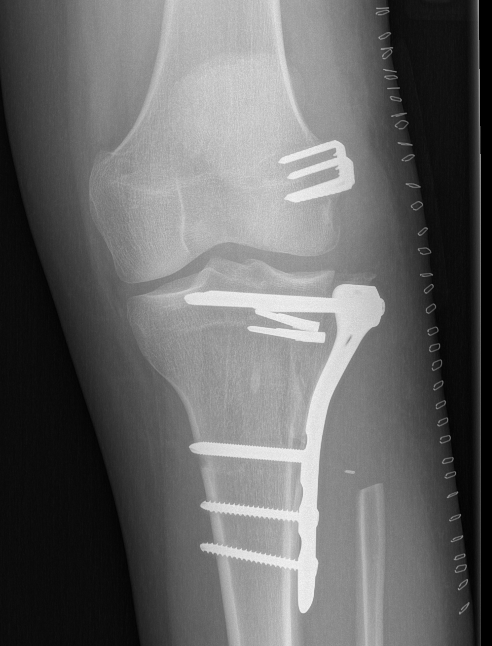

Technique

Cortical window

- burr / currette

- phenol / cryotherapy / liquid nitrogen